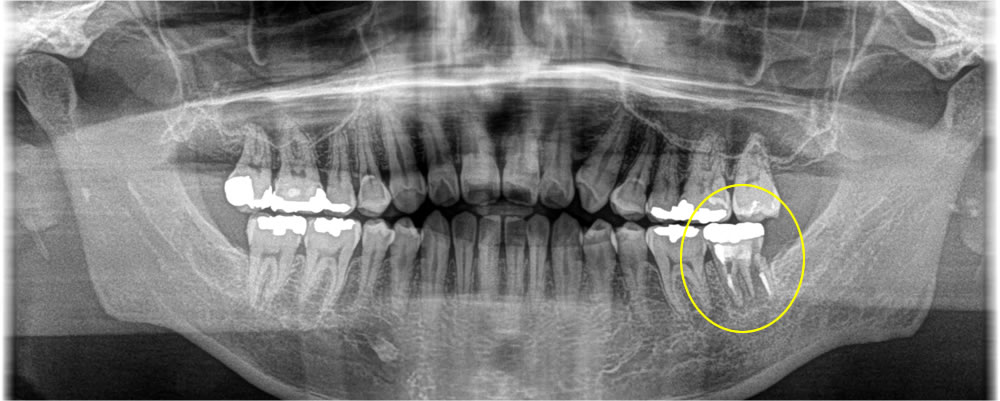

レントゲン検査の結果、過去に他院で治療した歯の根っこが割れていることが確認できました。歯根が破折してしまっており、歯を残すことが難しいため、破折歯を抜歯後にインプラントでの治療を選択されました。